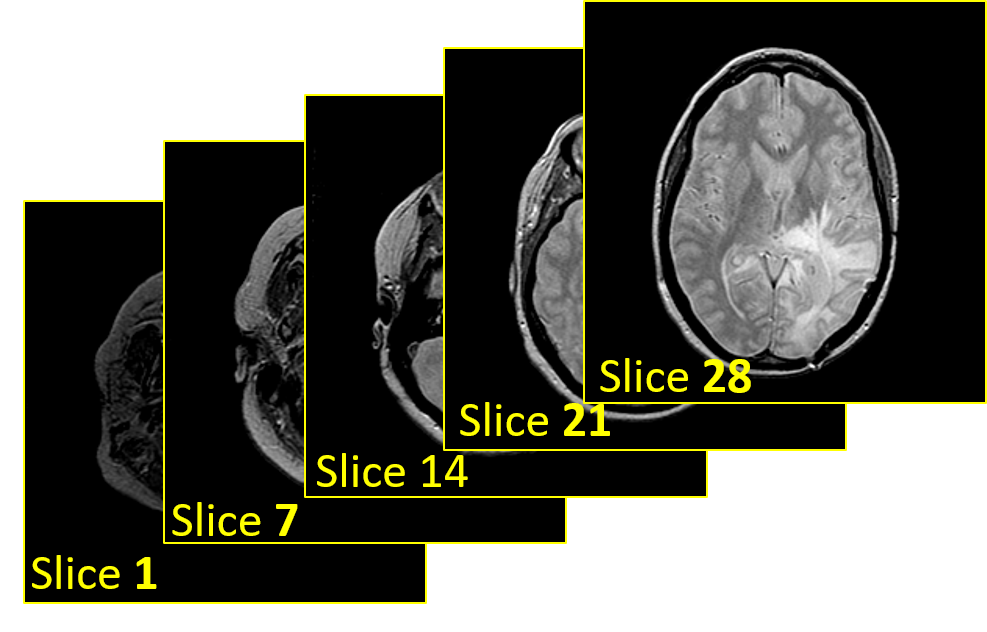

The objective of our work is to classify MRI images to predict the presence of neoplasms and their severity. In this experiment, an MRI dataset is collected from the online repository of The Whole Brain Atlasjohnson_becker . This website is maintained by Harvard Medical School and has proved to be very authentic in terms of medical imaging datasummers2003harvard . T2 weighted images are used in the experiment as shown in Fig. 9. The types of the MRI for malignant brain neoplasms in the dataset are glioma and sarcoma. And the benign brain neoplasms are metastatic bronchogenic carcinoma(M.B.C.), metastatic adenocarcinoma(M.A.) and meningioma. The shape of an MRI image is h ×\times w ×\times n, where n is the number of slices in each image, h is height and w is width, where h and w both equals to 256.

Refer to caption

Figure 9: Example of stacked brain MRI slices